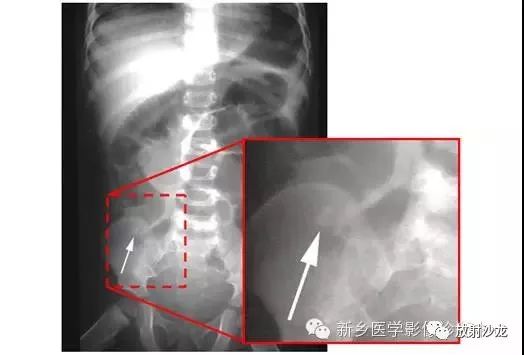

上图为一58岁男性,因1周前非特异性消化不良,行上消化道钡餐检查,做的腹部平片。患者最初表现为不确切的腹部不适和便血。现在又出现了腹痛和腹膜炎。箭头所指的典型表现是什么,诊断是什么?

箭头指向缺血穿孔性肠病患者的浅浮雕征。这也被称为双壁征或Rigler征。通常仅一侧肠壁可以看到。当双侧都能看到时,它表示腔内和腔外都有气体。当病人腹痛症状逐渐加重,肠壁穿孔是很有可能的。该患者手术过程中发现肠道脾曲缺血穿孔性肠病。